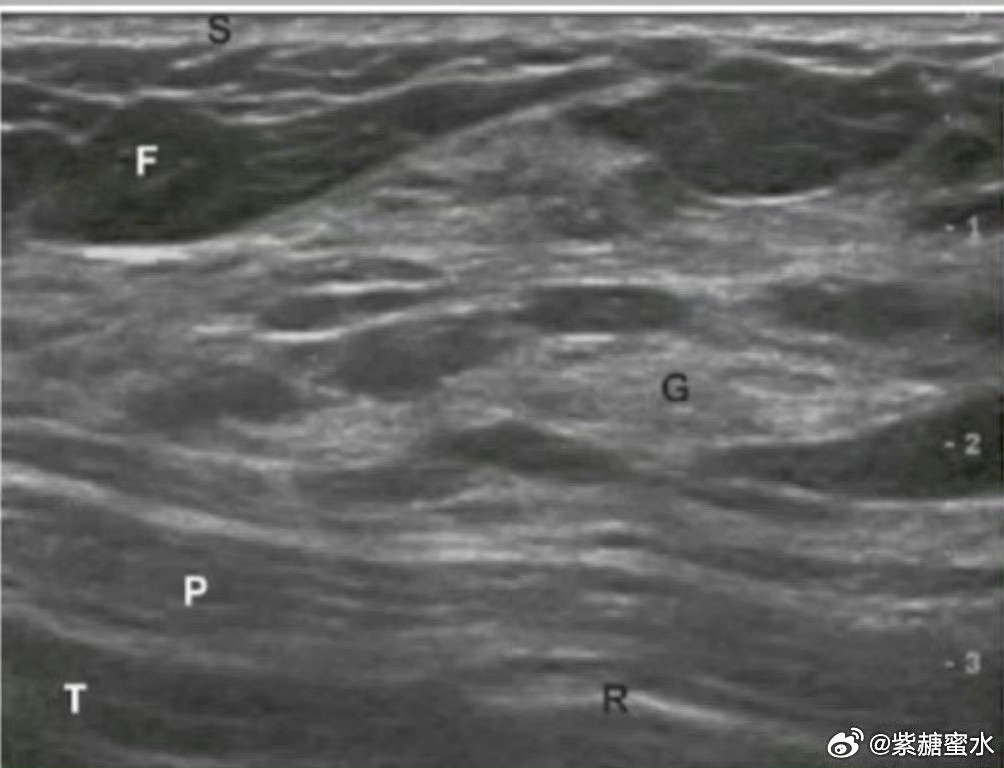

只有在合适的时间进行乳房B超检查,才可以清晰地显示从皮肤表面到胸壁的乳腺解剖结构。

正常乳房的超声影像,显示乳腺解剖结构